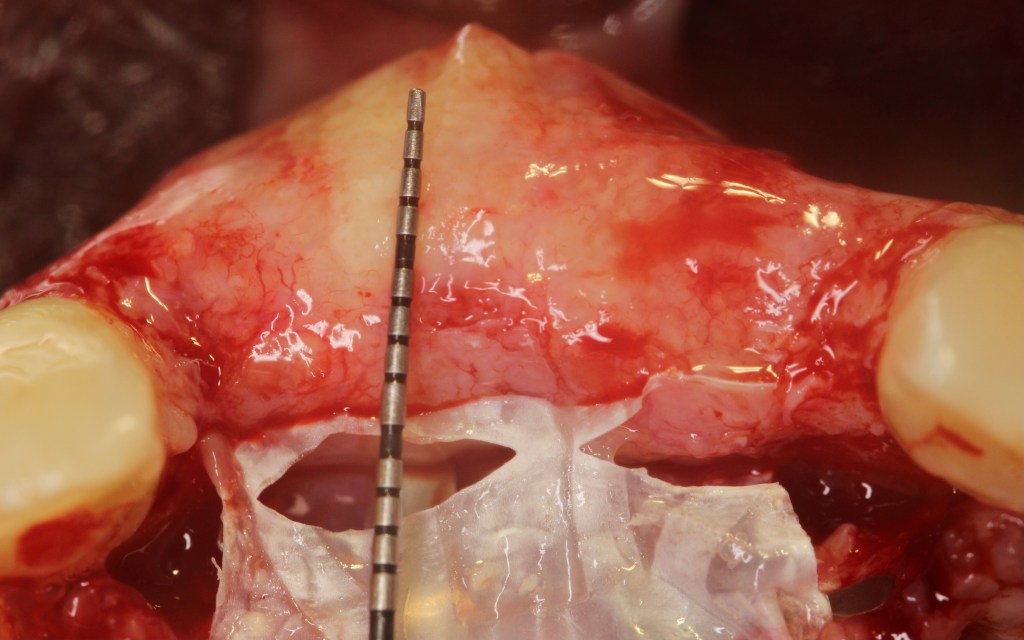

Vertical ridge augmentation in the anterior maxilla.

Anterior maxilla reconstruction.